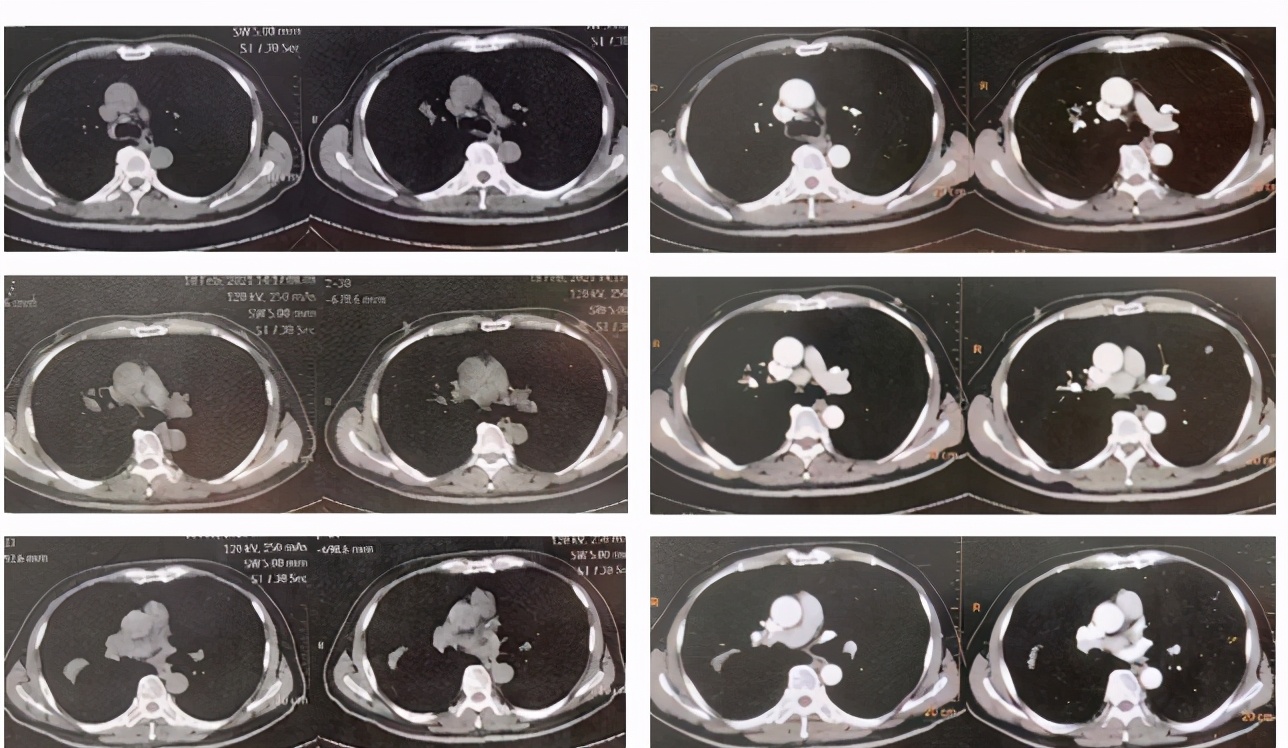

1年前肺CT(2020.3.12)

本次发病时肺CT(2021.2.18)

外院治疗后肺CT(2021.3.5)

1年前肺CT和发病时肺CT比较:

外院治疗前后肺CT比较:

黎庶教授(放射科)点评: 该患者的右肺门可见一团片影,其内可见正常走形的支气管,右肺上叶后段临近叶间胸膜处又可见一团片影,类圆形,边缘有毛刺,周围类似有晕征,除此之外肺内还可见多发散在的结节,边缘不规则。上述病灶经抗炎治疗没有改善,似乎有所加重。根据目前这些资料,无法确定感染还是非感染,一元论还是两元论,但肝癌肺转移肯定不是,因为肺内转移瘤不会形成大片状的改变,影像学不支持肝癌肺转移。肺CT改变更倾向于非感染,病灶沿支气管血管束旁和胸膜下分布,是多发的多种形态的,MALT淋巴瘤有这种特点,除此之外,炎性肌纤维母细胞瘤也有这种特点,血管炎、肉芽肿性病变也可出现。肺CT病变还有一个特点是既有实质改变又有间质改变,感染性疾病中TB、NTM和隐球菌都可以出现这种影像学改变。将肺脏和肝脏结合在一起分析,淋巴瘤可以同时多器官受累,风湿免疫系统疾病也可能。

刘宁教授点评: 肺CT病灶的形态是多样的,有结节影,有斑片影,有实质改变也有间质改变,单纯从肺CT看,这是不能排除肺结核的。肺结核可以合并肝结核,但是肝结核病灶一般位于包膜下,并且往往有钙化灶,做增强CT之后,中心是弱强化,周边因为有肉芽组织和纤维组织增生是环形强化,从这个角度来看,肝脏这个病灶不太符合肝结核的表现。肺部改变不能完全除外肺结核,肝脏不符合结核,这样分析的话就是两元论,但临床上一般多是一元论分析问题,所以反倒不支持肺部是结核了。

激素治疗前后肺CT